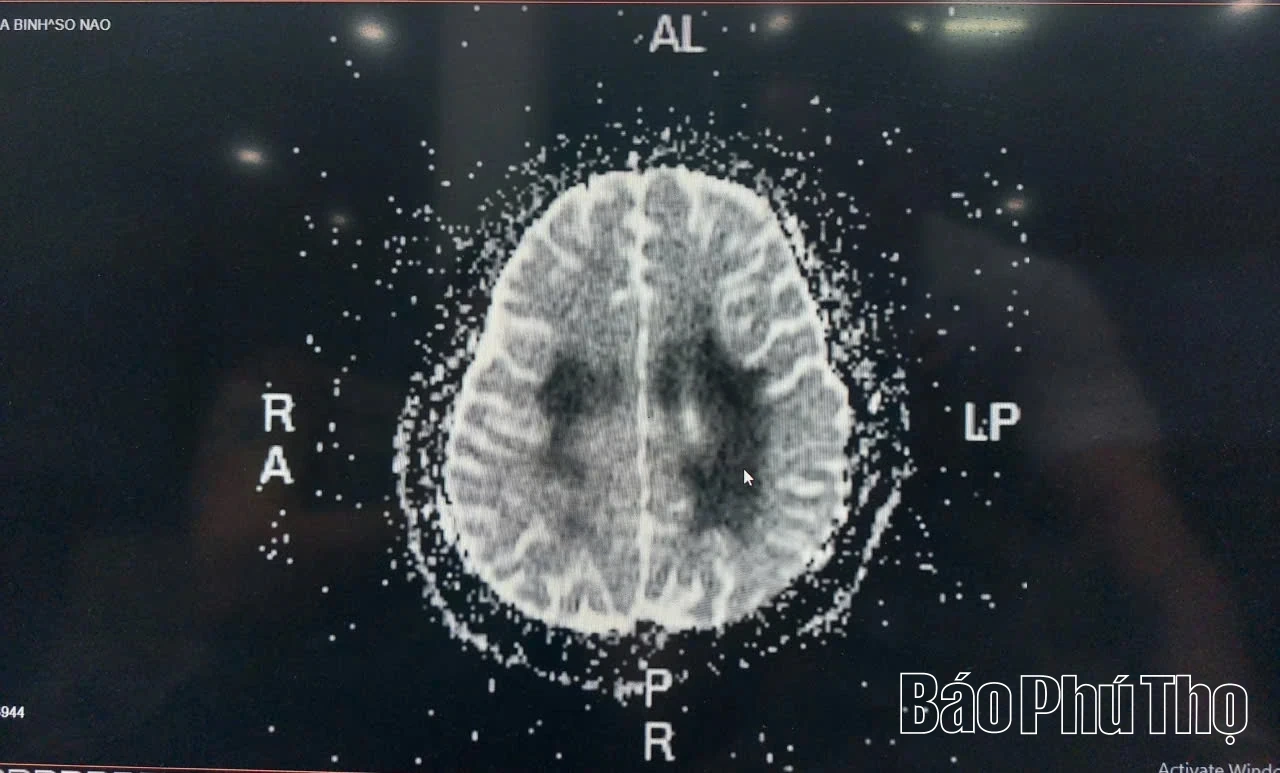

Hình ảnh chụp cộng hưởng từ não bệnh nhân bị tổn thương do ngộ độc hoá chất từ thuốc lá điện tử

Bác sĩ Tạ Huy Kiên, Trưởng Khoa Hồi sức cấp cứu, Bệnh viện Đa khoa Hoà Bình cho biết: Bệnh nhân B.T.T.L từ xã Quyết Thắng nhập viện ngày 6/8 trong tình trạng tê yếu nửa người phải, kích thích từng cơn, cảm giác nói khó, thay đổi tri giác. Qua chụp cộng hưởng từ và khai thác tiền sử kết luận: Bệnh nhân bị tổn thương não do nhiễm độc hoá chất từ thuốc lá điện tử.